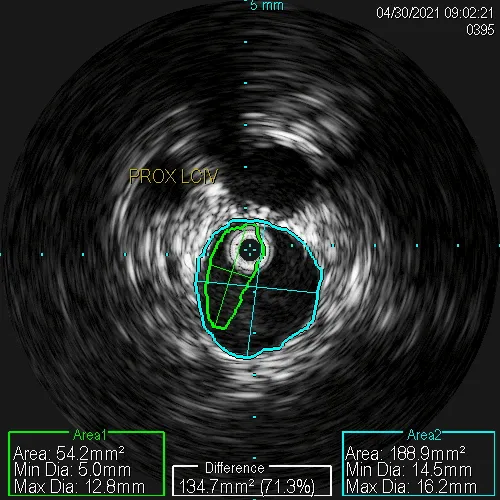

A catheter-based imaging tool that creates detailed pictures inside the vein to detect compression and guide treatment decisions.